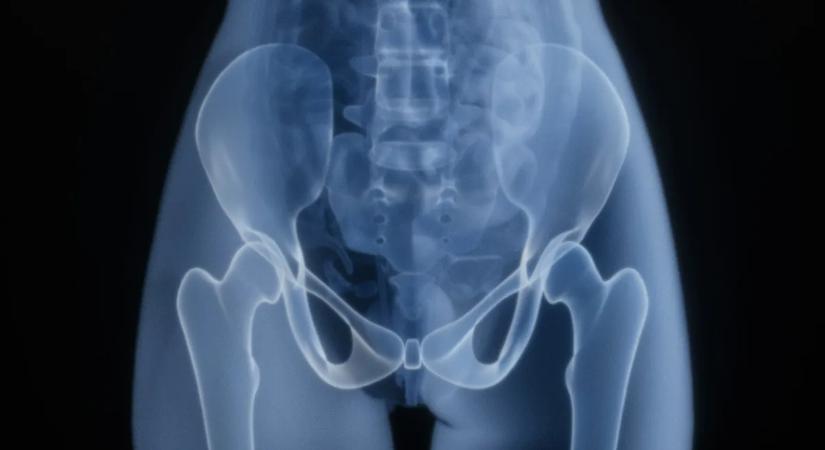

Csípőfájdalom? Ezekkel a tünetekkel azonnal forduljon orvoshoz! 2025.12.20. 05:37 Origo - Külföld csípő fájdalom Akárkit érinthet. Elolvasom a cikket >> - Hirdetés -